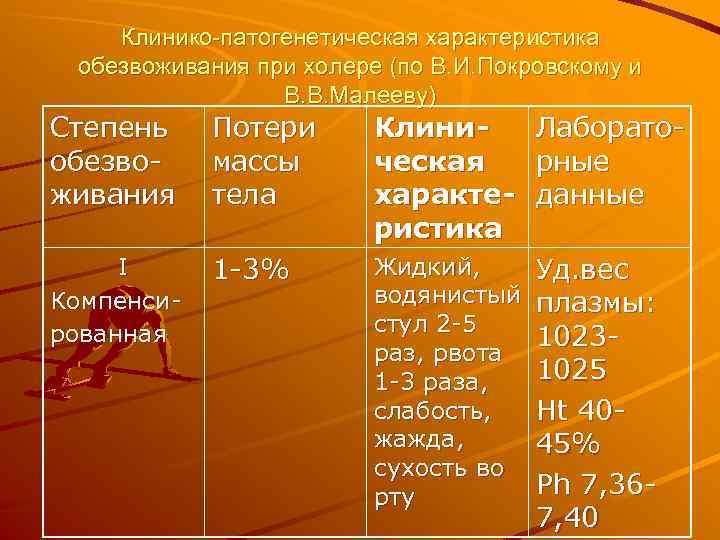

Клинико-патогенетическая характеристика обезвоживания при холере (по В. И. Покровскому и В. В. Малееву) Степень обезвоживания Потери массы тела I Компенсированная 1 -3% Клини. Лабораточеская рные характе- данные ристика Жидкий, Уд. вес водянистый плазмы: стул 2 -5 1023 раз, рвота 1025 1 -3 раза, слабость, Нt 40 жажда, 45% сухость во Рh 7, 36 рту 7, 40

II 4 -6% Стул до 10 -15 раз в виде Компе «рисового отвара» , н обильная многократная рвота, выраженная сирова слабость, -нная. головокружение, сухость кожных покровов и слизистых, сухость во рту, жажда, снижение тургора кожи, осиплость голоса, акроцианоз, изредка судороги икроножных мышц, стоп, кистей, тахикардия, умеренная гипотония. Уд. вес плазмы: 1023 -1025 Нt 45 -55% Рh 7, 33 -7, 36 У части Больных Гипокалиемия и Гипохлоремия

III 7 лабил 9% ь-ная компе нсация Многократный, обильный стул типа «рисового отвара» , многократная, обильная рвота, значительная слабость, головокружение, сухость слизистых и кожи, снижение тургора кожи, заостренные черты лица, неутолимая жажда, сухой язык, цианоз лица, акроцианоз, продолжительные болезненные судороги мышц верхних и нижних конечностей, осиплость голоса, гипотония, Уд. вес плазмы: 1030 -1035 Нt. 55 -65% Рh 7, 30 Гипокалием ия, гипохлорем ия, азотемия, лейкоцитоз палочкояде р-ный сдвиг влево